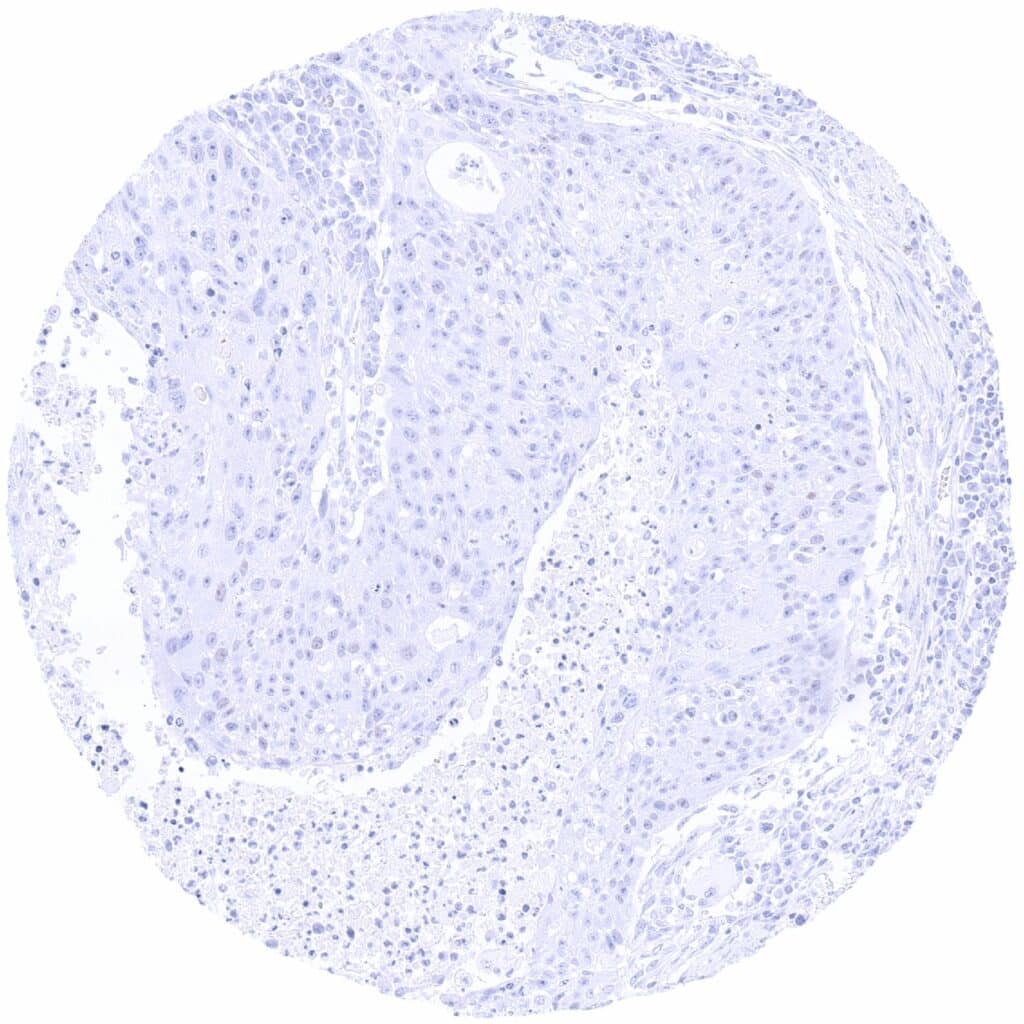

PAX6 antibody [MSVA-706M] HistoMAXTM

Lung – PAX6 negative squamous cell carcinoma